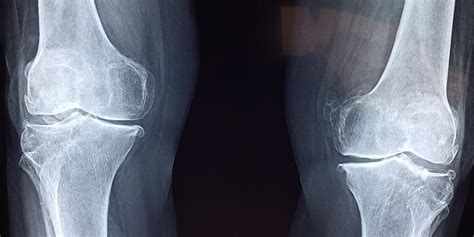

一:脊柱关节疾病:颈椎病、腰椎肩盘突出症、肩周炎、膝关节痛、骶髂关节炎、腰扭伤、腰椎滑脱、腰椎管狭窄、强直性脊柱炎、外伤性截瘫、腱鞘炎,网球肘、各类小关节扭伤、肌无力、肌萎缩、脑中风、冠心病、脊柱侧弯、梨状肌综合征、骨盆旋移、骨质增生等。